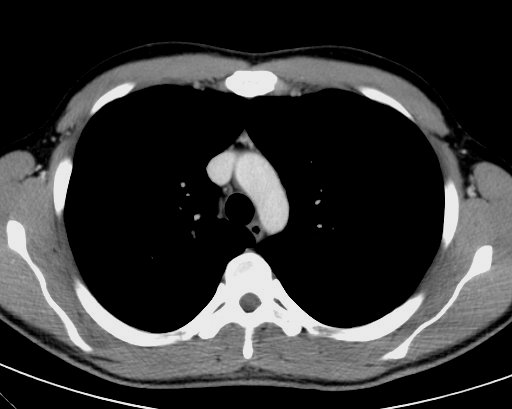

白色文字(排除指定关键词) Imaging Anatomy: interactive PACS-like atlas of radiological anatomy

解剖学模块